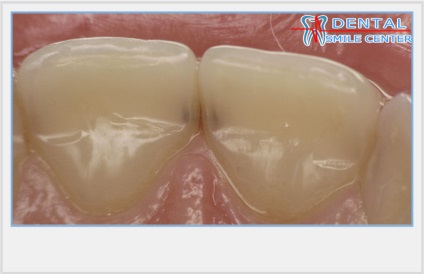

Sehol sem bővül, és ezért nem vesz részt a kialakulását az érintkező felületek. Ez a tulajdonsága a topográfia a fogak a korona és klinikai jelentősége - visszaállítási érintkező felületek csak átlátszó zománc árnyalatokat.

A frontális profilja az érintkező felületek az elülső fogak S-alakú, amely egy konvex rész és a konkáv rész.

A domború részét az érintkező felületek szintjén a legnagyobb szélessége a koronát képez két homlokegyenest kapcsolattartó pontok találhatók különböző magasságban. Két szomszédos érintkezési pontja két szomszédos fogak tartalmazhat egy kapcsolattartó pont, amelynek területe egyenlő a kb I mm-elülső fogak.

Klinikailag jelentős átmenetek vannak érintkezési felületek a vestibularis és száj felületén.

Az átmenet az érintkező felületek a vesztibuláris a henger felületét képez kellően hangsúlyos korlátozó reflexió zónában. Ez a zóna korlátozott, kivéve a marginális gerincek, és az egyenlítő a korona és a vágás.

Található egy ív mentén, a felső elülső fogak érintkeznek egymással csak orális felületeken, így fogközökbõl mindig legyen látható arci széle egybeesik a felület síkja terület gondolkodás, és ezért beeső fény és harmonikusan együtt. Hiánya metszőfogak a hajlamok olyan közös fény visszaverése orálisan (opistognatiya) vagy vesztibuláris (prognathia) vezet disbalance holisztikus felfogása a tervezési egység. Elmélkedés a fényviszonyok, így a fogak élénkebb és kifejezőbb észlelés mások nem csak abban az esetben könnyű fogakat, hanem ha a központi zóna reflexív fogak, mint homorú parabolatükörre vagy a felső oldalsó metszőfogak található a gépen a középső metszőfog, ha a trapéz alakú fogazat.